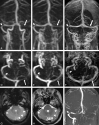

Fig 1.

Fifty-six-year-old woman with subacute left proximal lateral sinus thrombosis (duration of symptoms, 5 days). The arteriovenous transit of a contrast bolus is depicted on the dynamic series of combo-4D MRV (A–E; coronal MIP reformations of time-resolved contrast-enhanced MRV; temporal interval between images, 1.5 seconds). At early venous phase, faint filling of cortical veins and the superior sagittal sinus is noted (B). At subsequent later venous phase, the left proximal transverse sinus does not show increased contrast filling other than very faint peripheral enhancement of its dural wall (long arrow in C). At following later venous phases, no increase in contrast filling of this sinus portion is observed (long arrow in D and E). On axial static image of combo-4D MRV (contrast-enhanced 3D VIBE sequence), a hypointense filling defect within the proximal left transverse sinus is depicted (small arrow in F).